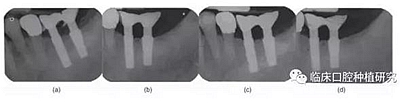

本研究的目的是評(píng)估種植體MicrothreadTM微螺紋結(jié)構(gòu)對(duì)維持種植體周邊緣骨水平的長(zhǎng)期效果的作用。通過(guò)對(duì)同一種植系統(tǒng)(Astra)的兩種種植體(Astra Tech Single Tooth:帶頸部微螺紋和AstraTech TiOblast:不帶微螺紋)的三年前瞻性觀察研究,發(fā)現(xiàn)頸部微螺紋設(shè)計(jì)有助于維持種植體邊緣骨水平穩(wěn)定。